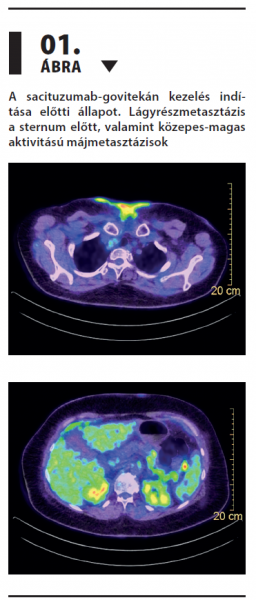

Antitest-gyógyszer konjugátum: sikeres terápia metasztatikus hormonreceptor-pozitív/HER2-negatív emlőtumoros beteg többedvonalas kezelése során